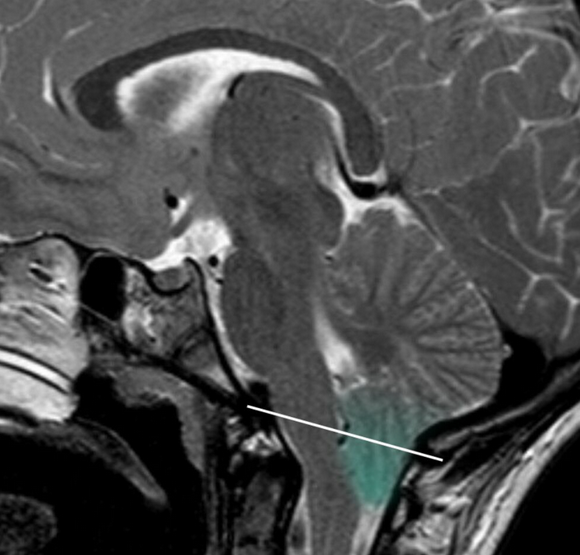

Chiari malformations are congenital abnormalities of the posterior fossa characterized by caudal displacement of hindbrain structures through the foramen magnum. MRI-based measurements assess the degree and pattern of descent of the cerebellar tonsils, vermis, brainstem, and associated posterior fossa anatomy. These measurements help distinguish Chiari subtypes, evaluate cerebrospinal fluid obstruction, and identify associated pathologies such as syringomyelia, hydrocephalus, or spinal dysraphism.

• Obtain midline sagittal MRI of the brain and craniocervical junction (T1 or T2).

• Identify the basion–opisthion line (McRae line) spanning the foramen magnum.

• Identify the foramen magnum reference line drawn between the basion and opisthion.

• Measure the vertical distance from this line to the lowest point of:

• Cerebellar tonsils (Type I)

• Vermis and brainstem structures (Type II)

3) Normal vs. Pathologic Ranges

• Normal: ≤3 mm below foramen magnum (some consider up to 5 mm borderline, especially in children)

• Pathologic: ≥5 mm tonsillar descent below the foramen magnum